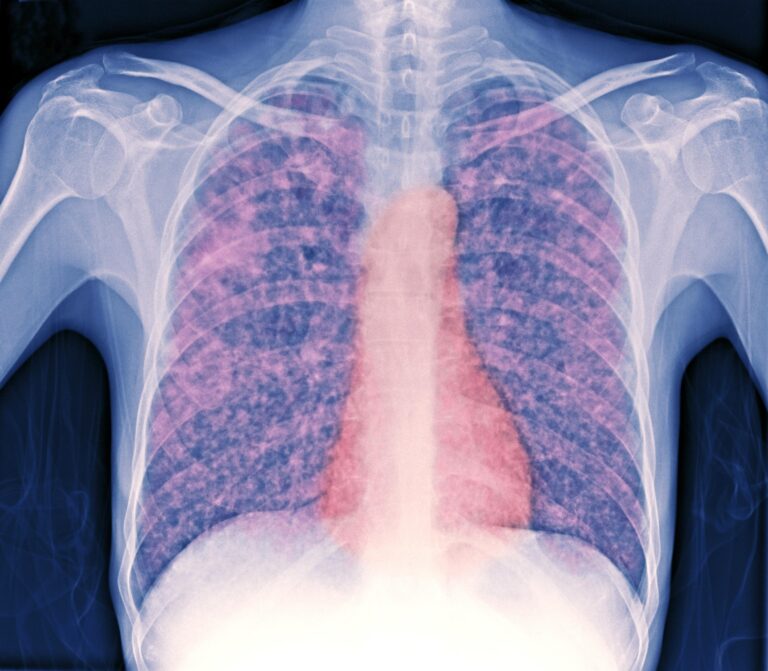

As tuberculosis (TB) cases continue to rise across the UK, health officials are increasingly alarmed by the trend, prompting heightened scrutiny on local statistics and region-specific interventions. Milton Keynes, like many cities, finds itself at the forefront of this public health concern. Recent figures indicate a concerning uptick in TB cases within the community, raising questions about the effectiveness of current prevention strategies and access to healthcare resources.In this article, we will delve into the latest data, explore the implications for public health in Milton Keynes, and examine the actions being taken to combat this resurgence of a disease that had once been largely under control. With the health and safety of the community at stake, understanding the local landscape is more crucial than ever.

The recent surge in tuberculosis (TB) cases within Milton Keynes has raised serious public health concerns, mirroring a broader trend observed across the UK. As health authorities scramble to combat this resurgence, local statistics reveal an alarming increase in confirmed cases over the past year. In 2022,Milton Keynes reported a 30% rise compared to previous years,highlighting the urgency for community awareness and intervention.Health officials attribute this spike to various factors, including delayed diagnoses during the COVID-19 pandemic, increased travel, and socioeconomic challenges that have affected access to healthcare.